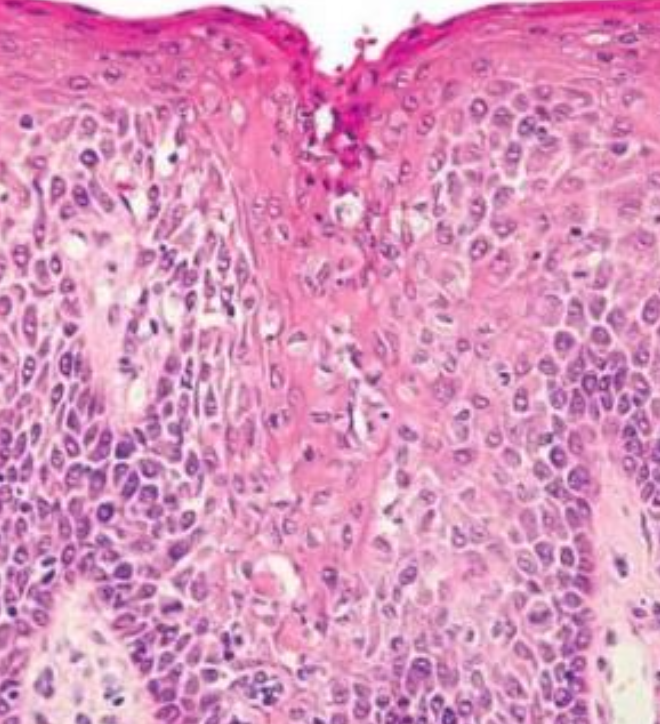

Hereditary Benign Intraepithelial Dyskeratosis

(HBID, Witkop’s disease)

體顯性

GENE: 4q35端粒, NLRP1, M77T

口腔與結膜黏膜,孩童

• 類似Cannon disease

• 眼睛: 不透明凝膠狀斑塊

• 舌背: 通常沒有影響

• hyperparakeratosis, acanthosis

• upper spinous layer 局部角化

• ell-within-a- cell